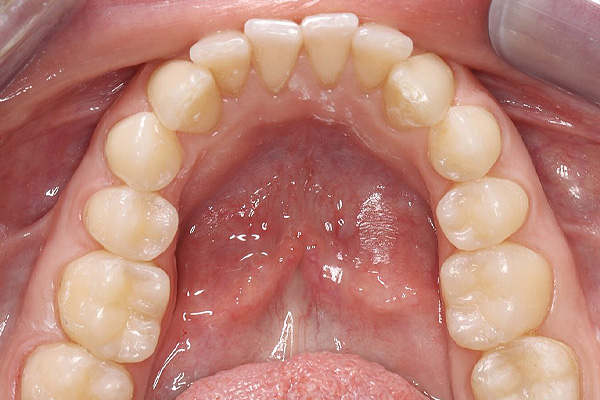

Terapinis gydymas Terapinis dantų gydymas – tai viena svarbiausių procedūrų, skirta suaugusiųjų ir vaikų burnos sveikatai išsaugoti. Šio gydymo metu efektyviai šalinamas dantų ėduonis (kariesas), restauruojami nuskilę ar nulūžę dantys bei keičiamos senos, nehermetiškos plombos. Taip pat atliekamas pleištinių defektų gydymas, padedantis apsaugoti apsinuoginusius dantų kaklelius nuo jautrumo ir tolesnio dylimo. Naudojant modernias medžiagas, atkuriama natūrali danties forma, spalva ir pilnavertė funkcija.Kas yra dantų ėduonis?Viena iš labiausiai paplitusių dantų ligų – dantų ėduonis (dar vadinama kariesu), kuri atsiranda dėl rūgščių dantų apnašų ir mikroorganizmų sąveikos. Laiku pastebėtas ėduonis išvalomas iki sveikų danties audinių, vėliau ertmė padengiama plombine medžiaga anatomiškai atkuriant danties formą ir funkciją. Pastebėjus ir laiku užkirtus kelią ėduonies atsiradimui ir plitimui – išvengsite didesnių problemų ateityje.Kodėl reikalingas dantų terapinis gydymas?Atsiradęs dantų jautrumas – kai dantys tampa jautrūs dėl dantenų atsitraukimo ar emalio nusidėvėjimo, tai gali sukelti diskomfortą valgant karštą, šaltą ar saldų maistą.Jei jaučiate kramtymo problemas – neteisingas dantų sukandimas gali sukelti įtampą žandikauliuose, galvos skausmus ir dantų dilimą.Dantų estetika – norint pagerinti dantų išvaizdą dėl estetikos priežasčių, pavyzdžiui, dėl tamsių dantų, netaisyklingos formos ar dydžio.Dantų skilimai ir lūžiai.Sąkandžio pakėlimas pagal pavaškavimąSakandžio pakėlimas pagal pavaskavimą (dar vadinamas „okliuzijos pakėlimu“) dažnai taikomas odontologijoje, kai siekiama koreguoti kramtomąją funkciją ir pagerinti sukandimo liniją.Kodėl reikalinga?Jei jaučiate dantų skausmą ar diskomfortą;Jaučiate įsitempusius žandikaulio ar veido kramtomuosius raumenis;Atsirado galvos skausmai;Jei jaučiate apatinio žandikaulio judėjimo sutrikimus.Atliekant sąkandžio pakėlimą gydytojas odontologas pirmiausia turi nusiimti paciento dantų atspaudą ir jį nusiųsti dantų technikams, kad būtų pagamintas pavaškavimas – kuris reikalingas gydytojui atkuriant dantų aukštį ir funkciją pagal dantų anatomiją.Dažnai užduodami klausimai (D.U.K.)Kiek laiko galima būti su laikina plomba?Laikina plomba dažniausiai dedama, kai tarp vizitų yra tarpai, ar po endodontinio gydymo keičiant į nuolatinę. Laikina plomba neturėti būti ilgiau nei 2-4 savaites, nes ilgainiui ji tirspta ir tampa pralaidi, gali iškristi.Kada galima valgyti po danties plombavimo?Jei buvo naudota vietinė nejautra, tuomet rekomenduojama palaukti, kol baigsis jos poveikis, kad nesukramtytumėte vidinės žando pusės. Jei nebuvo nejautros, tuomet galite valgyti iš karto, tačiau gydytojas odontologas perduos vis informaciją po vizito.Kiek kainuoja vieno danties plomba?Tiksli kaina priklauso nuo keleto veiksnių: pažeidimo gylio, plombinės medžiagos sunaudojamo kiekio, bei vizito metu naudojamų papildomų medžiagų ir priemonių (nuskausminimo, rentgeno nuotraukų ir t.t.)Paslaugos specialistai Visi Kaunas Vilkaviškis Visi specialistai Žilvinas Budrevičius Estetinių restauracijų specialistas, gyd. odontologasKaunas Inga Linkytė – Sližienė Estetinių restauracijų specialistė, gyd. odontologėKaunas Marius Kanopa Protezuojantis gyd. odontologasKaunas Odeta Bardijevskienė Estetinių restauracijų specialistė, gyd. odontologėKaunas Agnė Koncevičiūtė Estetinių restauracijų specialistė, gyd. odontologėKaunas, Vilnius Viktorija Šimkutė Dantų tiesinimo kapomis specialistė, gyd. odontologėKaunas Simona Pėčelytė Gyd. odontologė, specializuojasi vaikų ir suaugusių dantų gydymeKaunas, Vilnius Simona Pluščiauskaitė Gyd. odontologė, specializuojasi suaugusių dantų gydyme bei dantų šalinimeKaunas, Vilkaviškis Žemyna Binevičiūtė Gyd. odontologėKaunas Arūnė Mencevičienė Gyd. odontologėKaunas Austėja Valaškevičiūtė Gyd. odontologėKaunas Indrė Stočkė Gyd. odontologėVilkaviškis Lijana Linkevičiūtė Gyd. odontologė, specializuojasi vaikų ir suaugusių dantų gydymeVilkaviškis Žilvinas Budrevičius Estetinių restauracijų specialistas, gyd. odontologasKaunas Inga Linkytė – Sližienė Estetinių restauracijų specialistė, gyd. odontologėKaunas Marius Kanopa Protezuojantis gyd. odontologasKaunas Odeta Bardijevskienė Estetinių restauracijų specialistė, gyd. odontologėKaunas Agnė Koncevičiūtė Estetinių restauracijų specialistė, gyd. odontologėKaunas, Vilnius Viktorija Šimkutė Dantų tiesinimo kapomis specialistė, gyd. odontologėKaunas Simona Pėčelytė Gyd. odontologė, specializuojasi vaikų ir suaugusių dantų gydymeKaunas, Vilnius Simona Pluščiauskaitė Gyd. odontologė, specializuojasi suaugusių dantų gydyme bei dantų šalinimeKaunas, Vilkaviškis Žemyna Binevičiūtė Gyd. odontologėKaunas Arūnė Mencevičienė Gyd. odontologėKaunas Austėja Valaškevičiūtė Gyd. odontologėKaunas Simona Pluščiauskaitė Gyd. odontologė, specializuojasi suaugusių dantų gydyme bei dantų šalinimeKaunas, Vilkaviškis Indrė Stočkė Gyd. odontologėVilkaviškis Lijana Linkevičiūtė Gyd. odontologė, specializuojasi vaikų ir suaugusių dantų gydymeVilkaviškis Registruokitės terapiniam dantų gydymui ir pasirūpinkite savo šypsena su mūsų specialistų pagalba! Internetu +370 444 77777